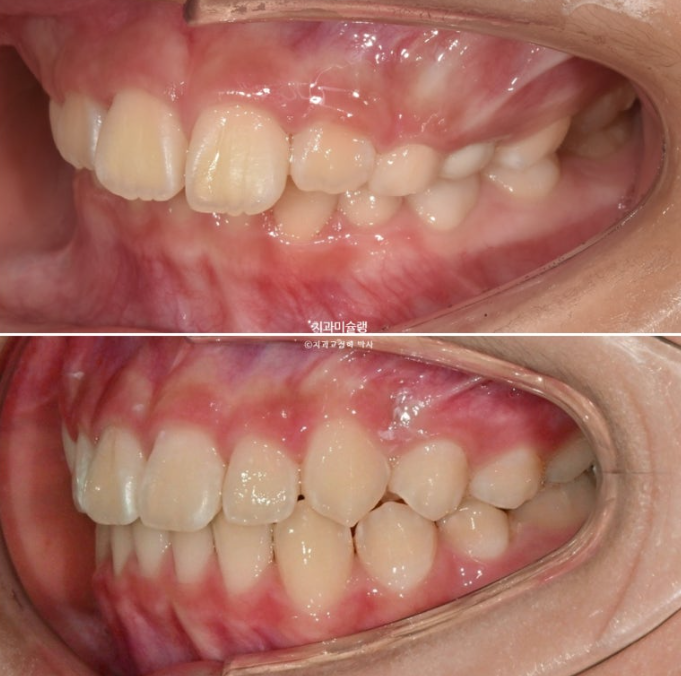

이제 전 후 비교 볼게요

23.10~25.11

과개교합과 중심선 불일치의 개선

완성된 교합은 1급 교합관계를 보입니다.